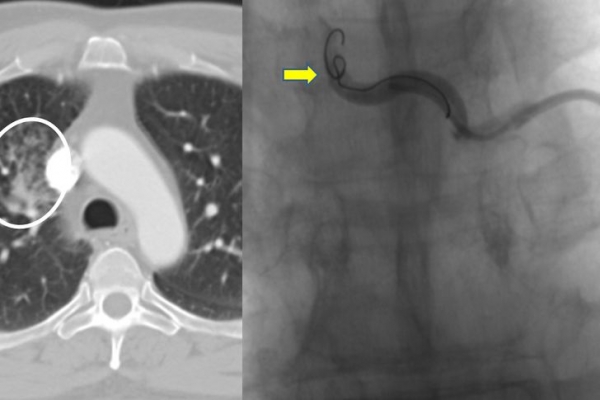

Υποτροπιάζουσα αιμόπτυση

Συνοπτικά υπό την καθοδήγηση του αγγειογράφου, αναγνωρίζεταιτο παθολογικό αγγείο-αγγεία και με ειδικούς καθετήρες και μικροκαθετήρες, διοχετεύονται εμβολικά υλικάόπως μικροσφαιρίδια ή coils, ώστε να αποφραχθεί ή να μειωθεί η παθολογική αγγείωση.